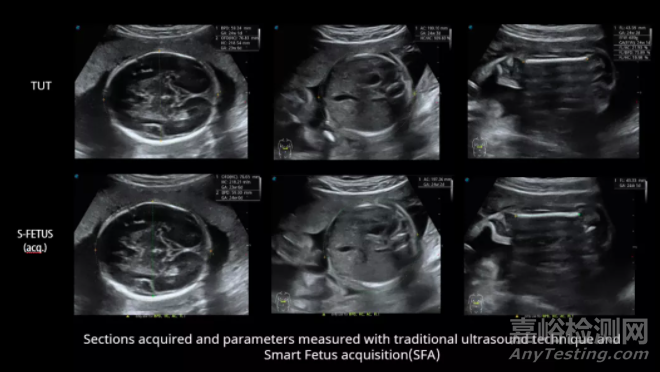

國內(nèi)某知名醫(yī)院對比了“鳳眼S-Fetus”與傳統(tǒng)超聲技術(shù)在16-41周正常胎兒標(biāo)準(zhǔn)切面獲取、切面識別以及自動測量的臨床應(yīng)用。對比結(jié)果顯示,S-Fetus技術(shù)對自動切面獲取的成功率可達99%以上,單次切面獲取的成功率可達95%以上;生長參數(shù)自動測量其準(zhǔn)確度可達99%以上,單次測量的準(zhǔn)確度可達98%以上。

使用“鳳眼S-Fetus”技術(shù)進行產(chǎn)科超聲診斷(從左到右:采集丘腦橫切面、丘腦腹部橫切面、股骨縱切面)